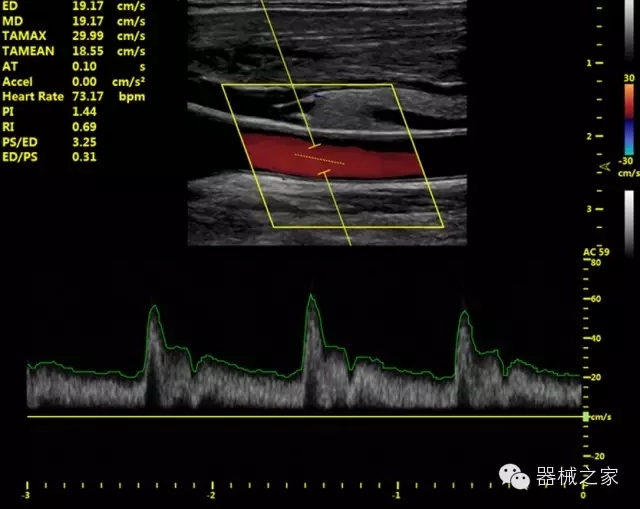

臨床圖片賞析

·獨(dú)有的HoloTM PW 實(shí)時(shí)3取樣門PW成像技術(shù),精確進(jìn)行血管診斷;

·一鍵優(yōu)化B、Color、PW,Auto Doppler自動(dòng)識(shí)別血管位置、偏轉(zhuǎn)角度等,提高工作效率;

·30°超廣角精細(xì)偏轉(zhuǎn)成像技術(shù),更優(yōu)異的頻譜圖像;